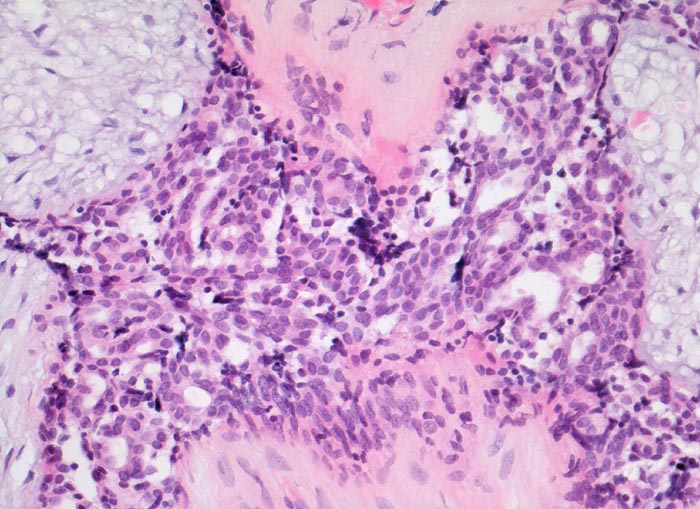

PathoPic – image database / PathoPic ID 3541 - Fibroadenom der Mamma: Epithelproliferation ohne Atypie

Fibroadenom der Mamma: Epithelproliferation ohne Atypie

Ausgeprägte Proliferation der epithelialen Komponente. Die proliferierten Zellen sind klein und zeigen keine zytologischen Atypien. Jeweils mehrere Zellen sind zu Strängen angeordnet und bilden ein fliessendes Muster. Zwischen den Strängen schlitzförmige Hohlräume. Das angrenzende Stroma ist zellarm und myxoid aufgelockert.

Scharf begrenzter frei beweglicher 3cm grosser derber Knoten im oberen äusseren Quadranten.

Die epitheliale Komponente von Fibroadenomen kann alle Veränderungen zeigen, welche auch im Mammaparenchym vorkommen (gutartige Epithelproliferationen, atypische Epithelproliferationen, Carcinoma in situ, invasives Karzinom...)